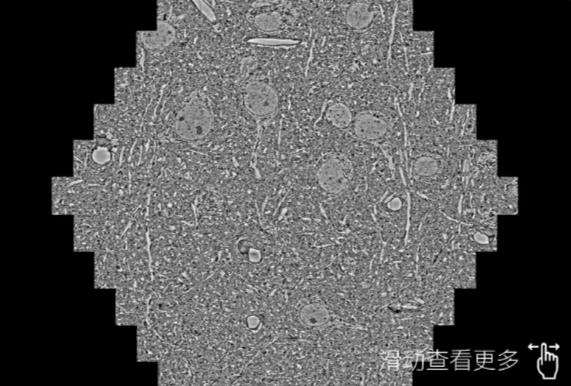

鼠脑切片。左图使用顺义蔡司顺义扫描电镜MultiSEM706对165μmx143pm面积区域成像,耗时仅需1.5秒。右图为鼠脑切片中30μm区域放大效果。样品由芝加哥大学B.Kasthuri提供。

使用蔡司高速顺义扫描电镜MultiSEM对1mm²人脑皮层组织进行高分辨成像,并对其中的各种细胞结构进行三维重构分析。左图展示了2x3mm²组织平面中锥体神经元的三维重构效果。右图显示了局部体积神经元三维重构。图像由哈佛大学chtman实验室提供,渲染图由D. Berger 制作。